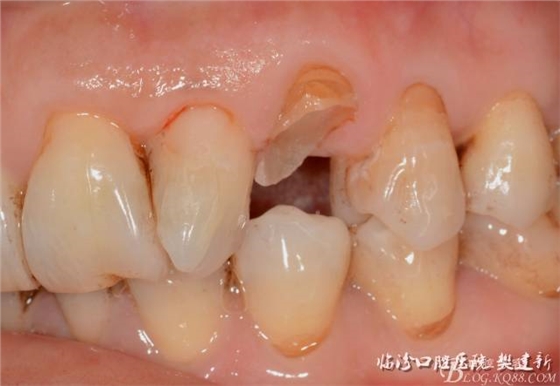

口內(nèi)檢查: 23殘根,位于齦上3MM,根管口探無反應(yīng),叩(+-),無松動,牙周無紅腫.X片示:23根管無阻射,根尖骨密度降低.11.12.13頸部楔形缺損,探敏感,牙髓活力正常.全口牙結(jié)石色素(+).

圖123口內(nèi)修復(fù)前情況:殘根位于齦上3MM,牙周無紅腫.